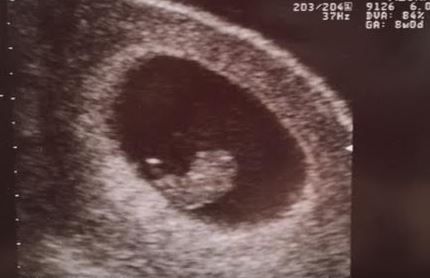

8w6d! Transvaginal. He/she was a little wiggle worm when the Dr first turned the machine on